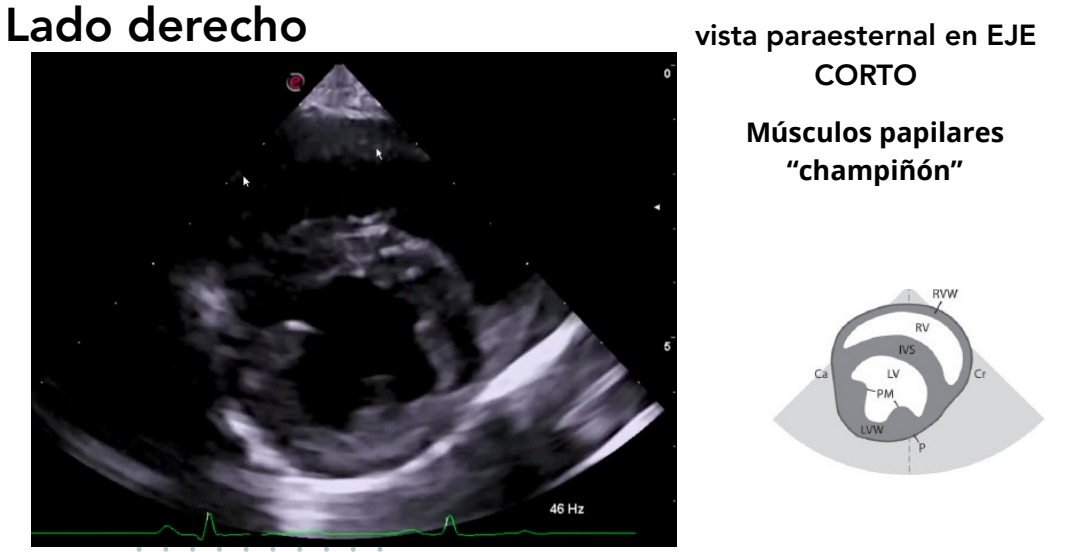

Vista paraesternal en eje corto

- Niveles observables:

- Músculos papilares ("champiñón")

- Válvula mitral ("boca de pez")

- Base cardíaca

- Tracto de salida del ventrículo derecho